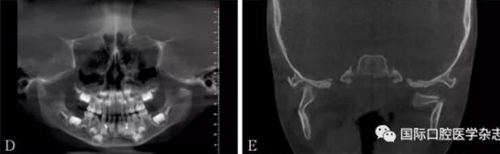

頜面部上下頜骨、顴骨及顴弓骨折、骨折片移位壓迫咀嚼肌群和下頜骨喙突,影響下頜骨的活動而造成張口受限[10-12](圖 9、10)。

A:患者面像;B:口內(nèi)像;C:三維成像;D:全景片;E:冠狀位。

圖 9 面部外傷

左:顴弓骨折CT平掃;右:顴弓骨折CT三維成像。

圖 10 顴弓骨折